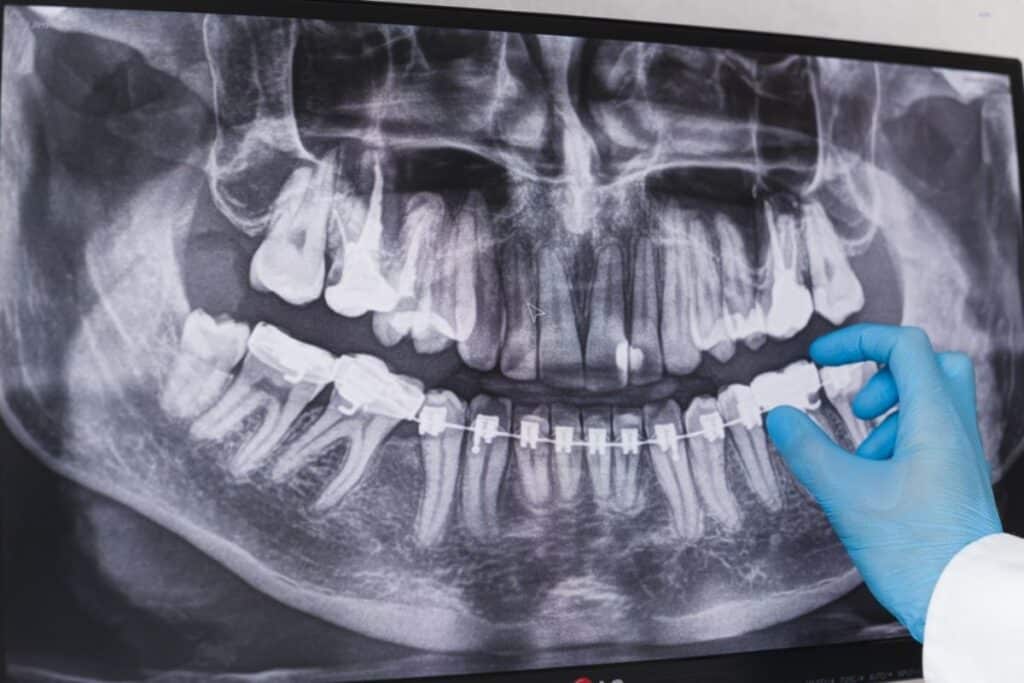

Parents often wonder when is the right time for their child to begin orthodontic treatment. You might have heard about early orthodontic care or Phase I treatment and thought — if my child starts early, will they still need braces later? Understanding how early intervention works and its long-term benefits can help you make the […]